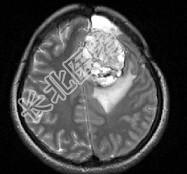

- 单项选择题女,39岁, 三年前因左额部胶质瘤手术治疗,最近出现头痛, 并抽搐大发作1次,请根据所提供图像, 诊断最有可能是 ( )

A、(左额叶)脑脓肿

B、(左额叶)脑出血

C、(左额叶)星形细胞瘤Ⅱ~Ⅲ级

D、(左额叶)脑转移瘤

E、(左额叶)放射性脑炎